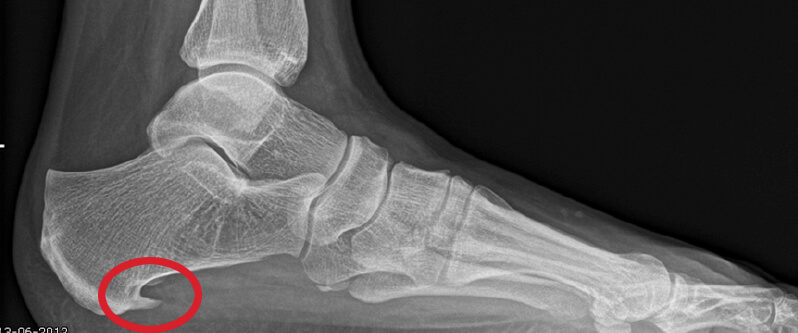

Een hielspoor is een verkalking aan de onderkant van het hielbot (calcaneus). Deze zit bij de aanhechting van de peesplaat die naar de voorvoet loopt. Een hielspoor is waarneembaar op röntgenfoto, maar ook is hij goed te zien op een echo.

Deze oorzaken hebben alles te maken met het feit dat op de peesplaat een langdurige druk wordt uitgeoefend. Als gevolg hiervan zal het lichaam reageren en ontstaat er een vergroeiing van het van het bot (verkalking) aan het hielbot, waar de peesplaat is aangehecht. De pijn die u kunt voelen heeft te maken met een ontsteking die de hielspoor kan veroorzaken in de peesplaat. De hielspoor zelf doet geen pijn.